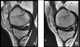

Microfracture

Microfracture surgery is an articular cartilage repair surgical technique that works by creating tiny fractures in the underlying bone. This causes new cartilage to develop from a so-called super-clot. [Source: Wikipedia ]